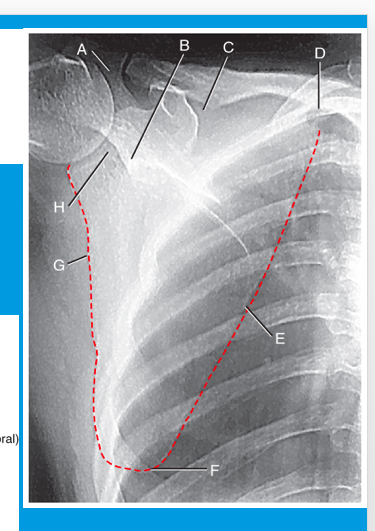

A

neck of scapula

B

suprascapular notch

C

superior angle

D

medial (vertebral) border

E

inferior angle

F

lateral (axillary) border

G

glenoid fossa

H